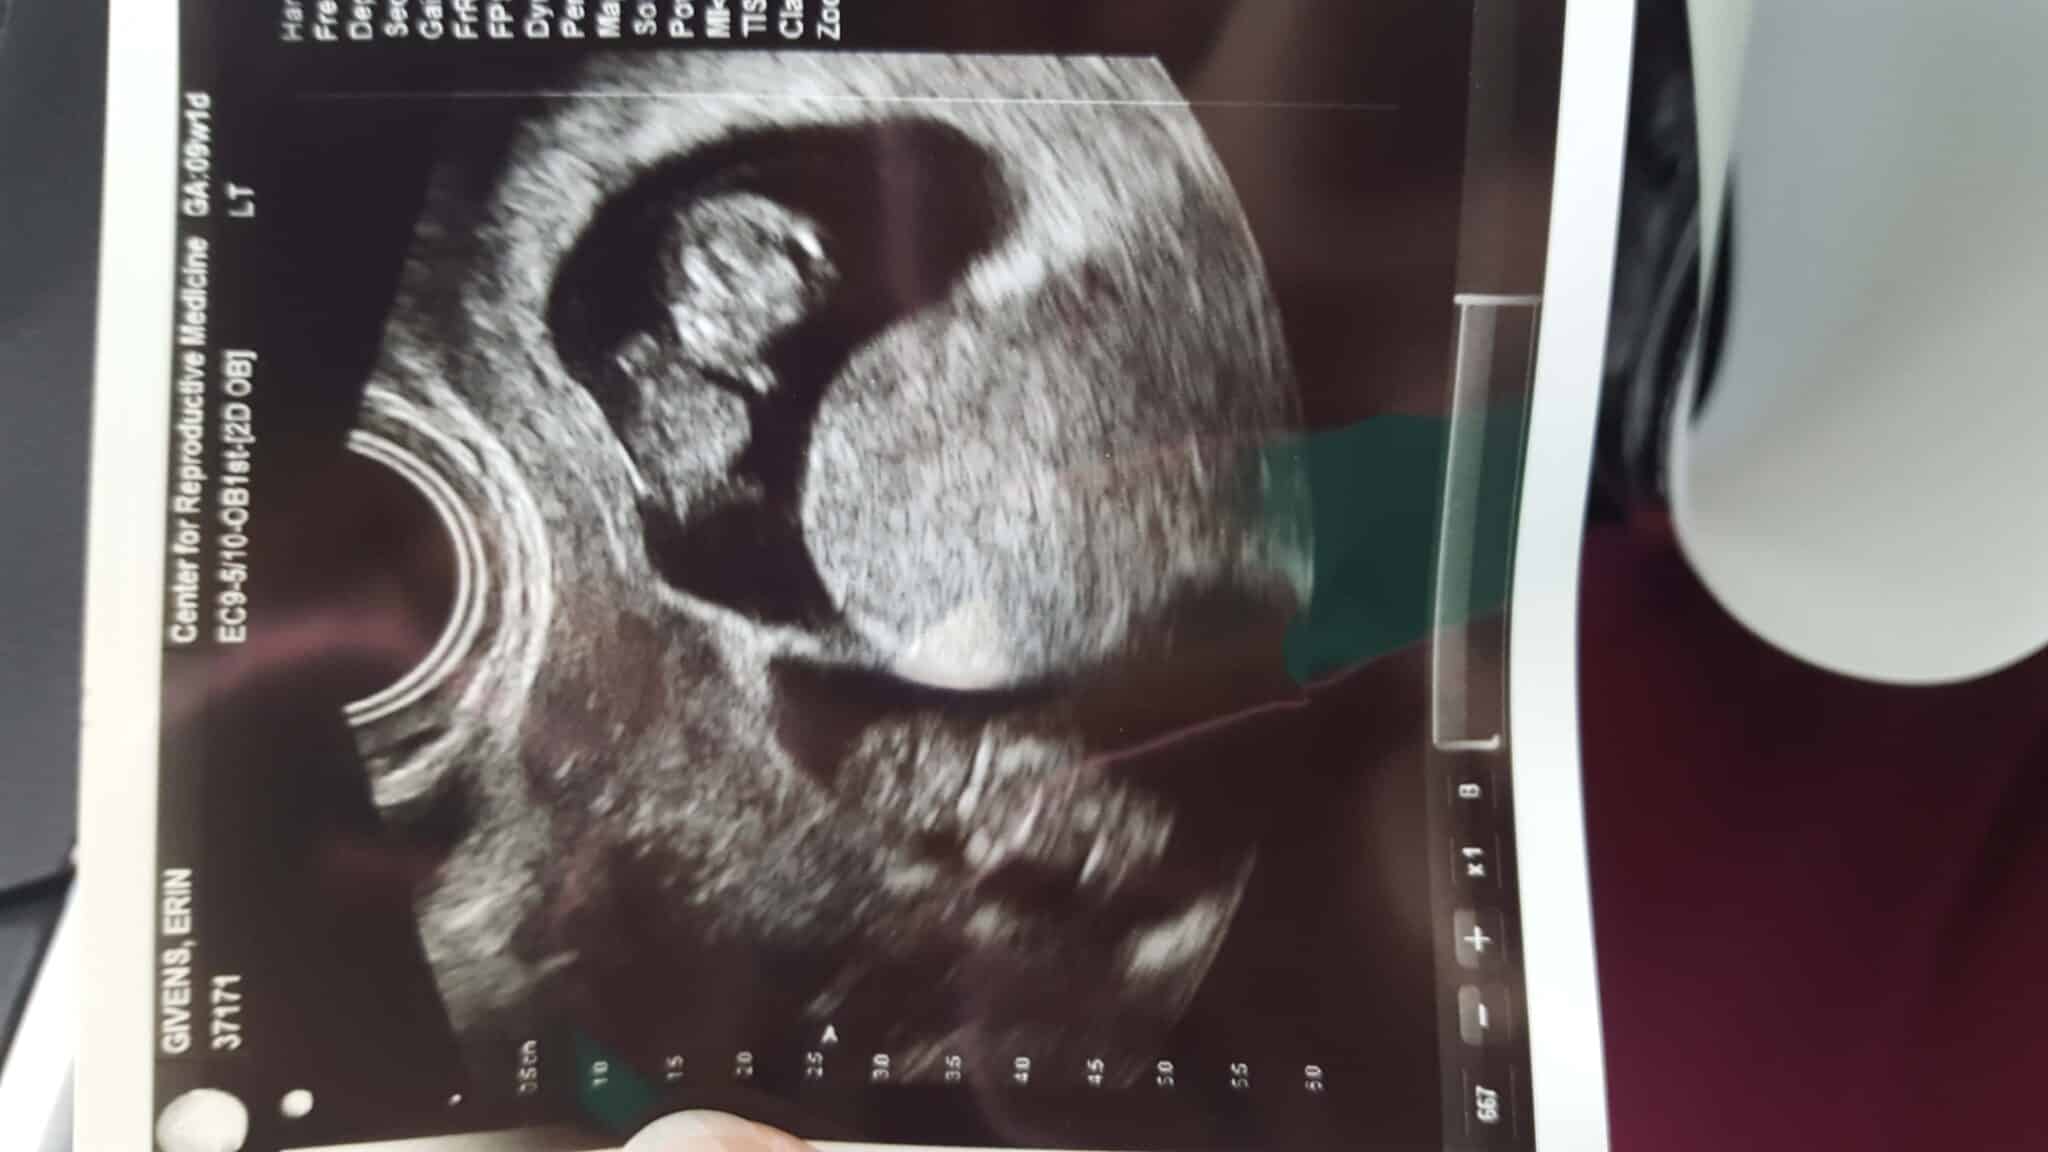

- Ultrasound Photos of 9 Weeks Pregnant With Twins

Ultrasound Photos of 9 Weeks Pregnant With Twins